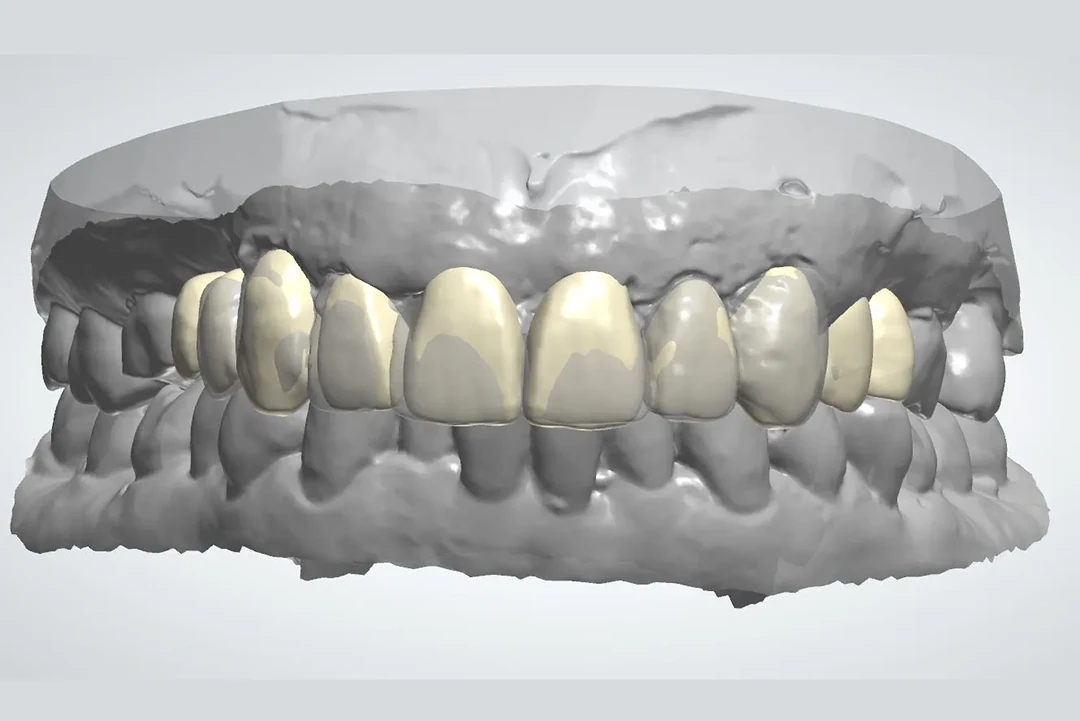

Somos Alzamora Dental, una clínica de referencia en Rubí especializada en cirugía guiada y carga inmediata, una técnica avanzada que permite colocar implantes dentales junto a una prótesis provisional en un solo día, siempre que el caso lo permita. Gracias a la planificación digital en 3D y al uso de una guía quirúrgica personalizada, la intervención es más precisa y mínimamente invasiva. Esto se traduce en menos tiempo de cirugía, menores molestias postoperatorias y una recuperación más rápida, con un resultado estético inmediato y altamente predecible.

De 61 años nos visita con dientes dañados por caries y una prótesis antigua que ya no podía utilizar. Gracias a la planificación digital y la cirugía guiada, realizamos las extracciones y colocamos implantes con una prótesis fija el mismo día. Recuperó su sonrisa y la confianza de inmediato.